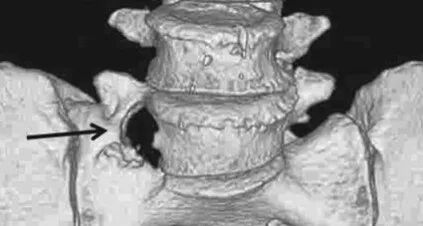

IIIa型:三维CT显示右侧横突与骶骨嵴融合

以目前国内的现状,首选薄层CT扫描并进行三维重建。